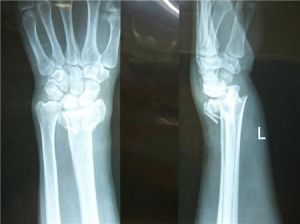

3、X線照片顯示骨折線模糊,有連續性骨痂通過骨折線;

2.原始骨痂形成期骨內、外膜增生,新生血管長入,成骨細胞大量增生,合成並分泌骨基質,使骨折端附近內、外形成的骨樣組織逐漸骨化,形成新骨,即膜內成骨。由骨內、外膜緊貼骨皮質內、外形成的新骨,分別稱為內骨痂和外骨痂。填充於骨折斷端間和髄腔內的纖維組織逐漸轉化為軟骨組織並鈣化形成骨,即軟骨內成骨,形成連線骨痂。連線骨痂、內骨痂和外骨痂相連形成橋樑骨痂,其標誌著原始骨痂形成。這些骨痂不斷鈣化加強,當其達到足以抵抗肌收縮及成角剪力和鏇轉力時,則骨折已達到臨床癒合,在成人一般約需12~24周(人衛版外科學教材第8版最新修改)。此時X線片上可見骨折處四周有梭形骨痂陰影,但骨折線仍隱約可見。對骨外膜的損傷均對骨折癒合不利。